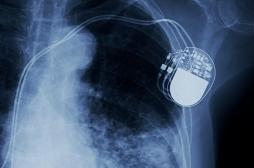

arrêt cardiaque